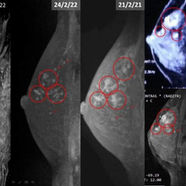

After the surgery, I continued traveling. I travelled for years. In 2024, I began to realize that the tumor had started growing again. I tried everything that was possible with alternative treatments, but I could see that it was growing very rapidly out of control. Over the following months, it grew rapidly. Imaging revealed a large, lobulated mass measuring approximately 44 × 50 mm. The skin over the breast became tense, discoloured, and painful, especially at night. An enlarged axillary lymph node raised further concern as well.

By December 2025, PET-CT imaging showed a clear and significant treatment response for my resolution of TNBC Ki-67 of 90%:

– Liver metastases had markedly reduced in size and metabolic activity

– Bone lesions were less active

– Lung nodules showed improvement

– The ulcerated breast tumour had become significantly smaller

This gave me a lot of hope. It confirmed what I do is heading to the right direction.